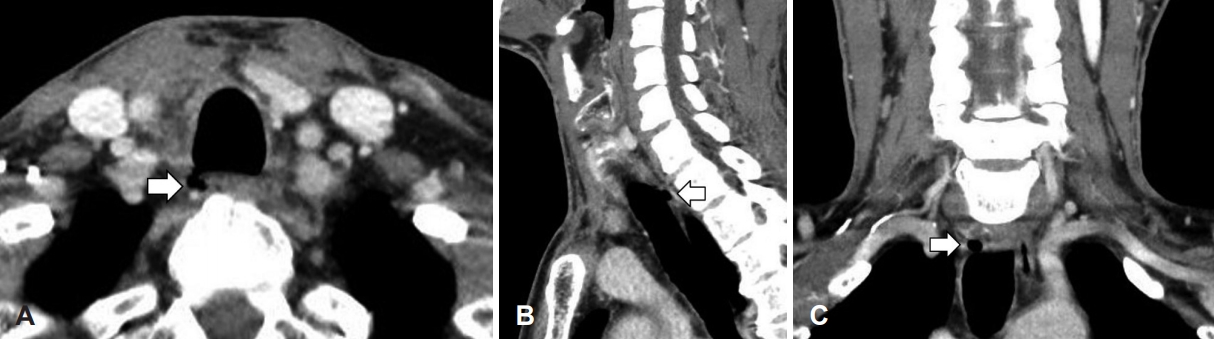

병리조직 검사 결과는 급성 화농성 감염 소견을 동반한 지방 조직이 보였고, 결핵 중합효소 반응 검사에서 음성이었다. 술 후 3일째에 시행한 전산화단층촬영 검사상 기관 주위에 종물의 염증성 소견은 호전이 없었고 다른 후인두 병변들은 호전되었다(Fig. 3). 인후통, 발열 증상은 호전되었으며, 혈액 검사상 백혈구 4.71(×103/μL, 3~9.3), 분엽 호중구 44.3(%,40~70), 적혈구침강속도 58(mm/hr, 0~30), C-반응단백 0.56(mg/dL, 0~0.5)으로 염증 수치의 호전 양상을 보였다. 다학제적 회의 후 기관 낭종의 감염으로 인한 후인두 농양으로 진단되었다. 환자는 특별한 합병증 없이 수술 후 10일 뒤 퇴원하였다. 2개월 뒤 외래에서 추적 검사로 시행한 전산화단층촬영상 우측 기관 주위 농양강은 대부분 줄어들었으며, 농양이 있었던 기관의 우측 후방부에서 낭종이 발견되었다(Fig. 4). 기관에서 낭종 확인을 위해 기관내시경을 시행하였으나 연결 부위나 다른 특이 소견은 보이지 않았다. 기관 낭종의 염증 소견이 호전되었고, 염증이 동반되는 경우가 드물기 때문에 향후 재발 시 근치적 수술을 고려하기로 하였다. 수술 후 1년간 외래 경과 관찰 중 염증의 재발 소견은 없고, 영상 검사에서 낭종의 변화 소견은 없었다.

기관 낭종을 진단하기 위해 초음파, 컴퓨터단층촬영, 기관지 내시경 등이 사용된다. 초음파에서 기관 낭종은 보통 반향허상(reverberation artifacts)이 동반된 저음영의 종괴 소견을 보인다[3]. 기관 주위 종괴 소견이 보일 시 결핵성 림프절염 및 전이성 림프절염 등을 배제하기 위해 수술 전 생검을 먼저 고려해야 한다. 컴퓨터단층촬영은 기관 낭종의 크기와 위치, 형상, 그리고 기관과 연결된 부위 등을 파악하기에 가장 유용하며 대부분 흉추 1번에서 2번 높이에서 우측 후하방으로 나타난다[5]. 본 증례에서도 가장 나중에 시행한 컴퓨터단층촬영에서 기관 낭종은 흉추 1번 높이에서 발견되었다. 기관 낭종은 보통 크기가 작기 때문에 선행 정보가 없는 경우에는, 기관내시경으로 연결된 부위를 놓치는 경우가 있을 수 있다[10]. 또한 Zenker 게실과 같은 기관 낭종의 식도 연결을 확인하기 위해서는 식도내시경이나 식도 조영술이 필요할 수도 있다[11].